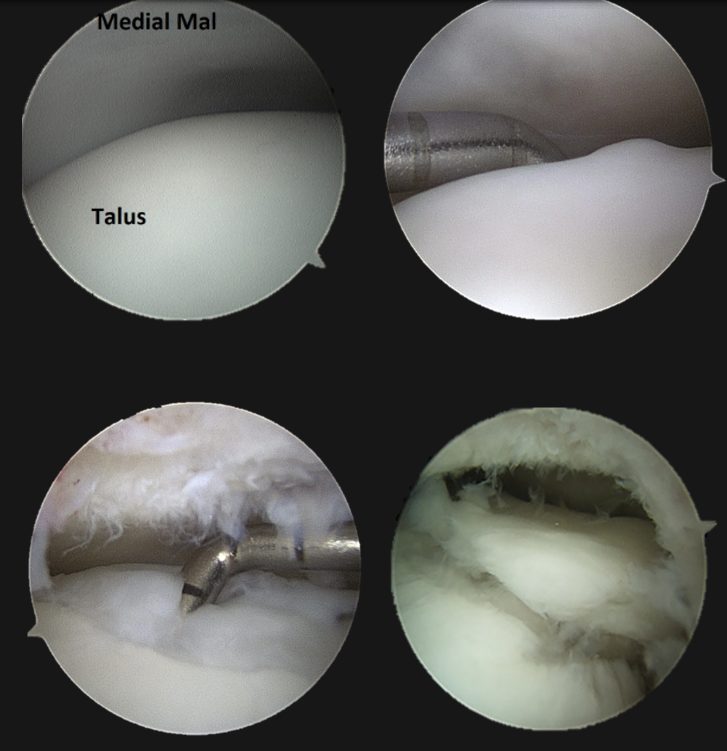

Рис. 9. Артроскопический вид различных стадий остеохондральных повреждений таранной кости

Костномозговая стимуляция (BMS / микрофрактуринг)

Техника (артроскопическая):

- Диагностическая артроскопия через стандартные порталы (передне-медиальный рабочий, передне-латеральный обзорный)

- Идентификация и оценка ОХП пробником

- Дебридмент: удаление нестабильного хряща малой кюреткой. Стабильные края хряща сохраняются и формируются вертикально (perpendicular) для удержания кровяного сгустка

- Удаление склеротической субхондральной пластинки кюреткой

- Микрофрактуринг: перфорация субхондральной кости шилом (awl, обычно 60-65°) перпендикулярно поверхности. Отверстия на расстоянии 3-4 мм друг от друга. Глубина — до появления жировых капель (fat droplets), что подтверждает проникновение в костный мозг

- Снижение давления ирригации → визуализация кровотечения из перфорационных отверстий (подтверждение эффективности)

- Формирование стабильного кровяного сгустка (super clot)

Рис. 10. Артроскопическое микрофрактурирование субхондральной пластинки